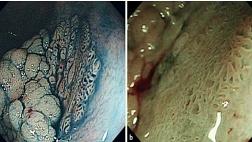

Рис. 2. 24a – c Повреждение слизистой, вызванное лекарственными средствами: шкала Ланца. Медикаментозный эрозивный гастрит (Ланца Grade 1). b Легкий лекарственный геморрагический гастрит (степень 2 по Ланце). c Обширные язвы, вызванные лекарственными средствами, вдоль большой кривизны (степень 4 по Ланце).